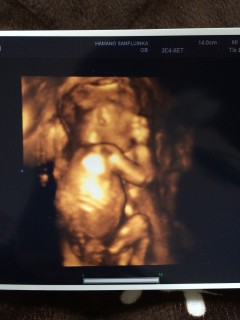

写真:18w5d:まむさん:踊ってる?

初めての4Dエコーでした! 頭の大きさ44.0ミリ、足の裏の大きさ29.9ミリで週数相当とのこと。 オマタに尖ったものが見えましたが、タマタマが見えないので性別確定はしませんでした(TT) 不妊治療でやっと授かった子なので、とにかく健康で元気に産まれてきてくれれば何よりです!